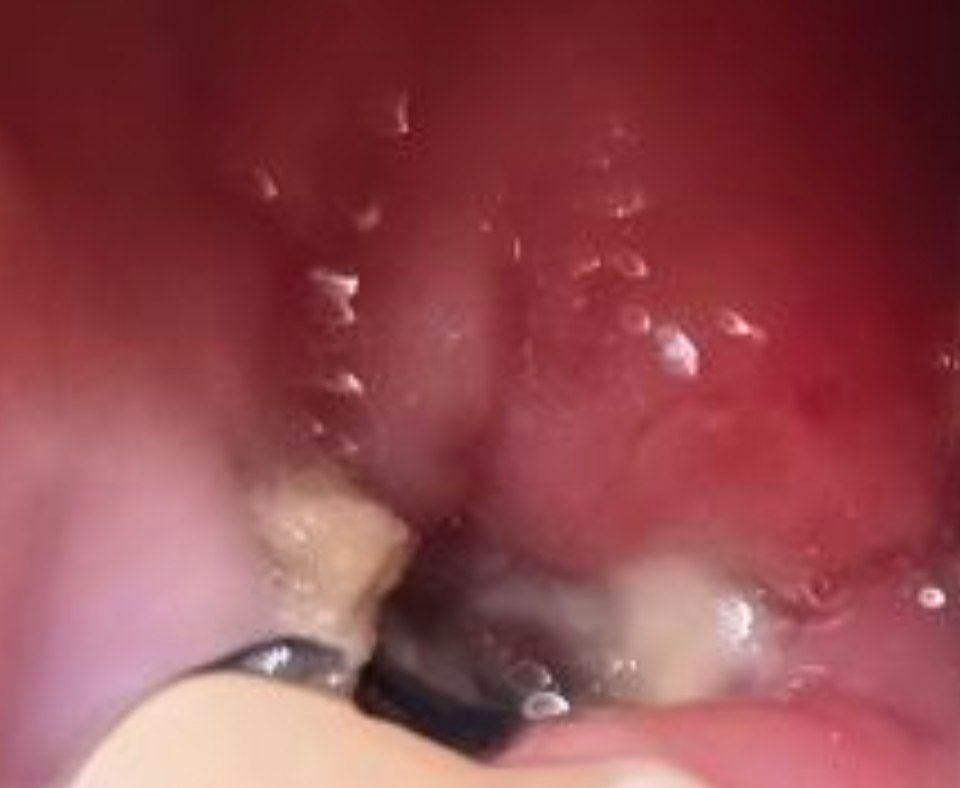

죽으로 저녁 먹다가 실밥이 풀렸어요ㅠ

사랑니 4일때 되는날인데 실밥이 죽으로 저녁 먹다가 풀렸는데 괜찮을까요??

• 1번 째 사진